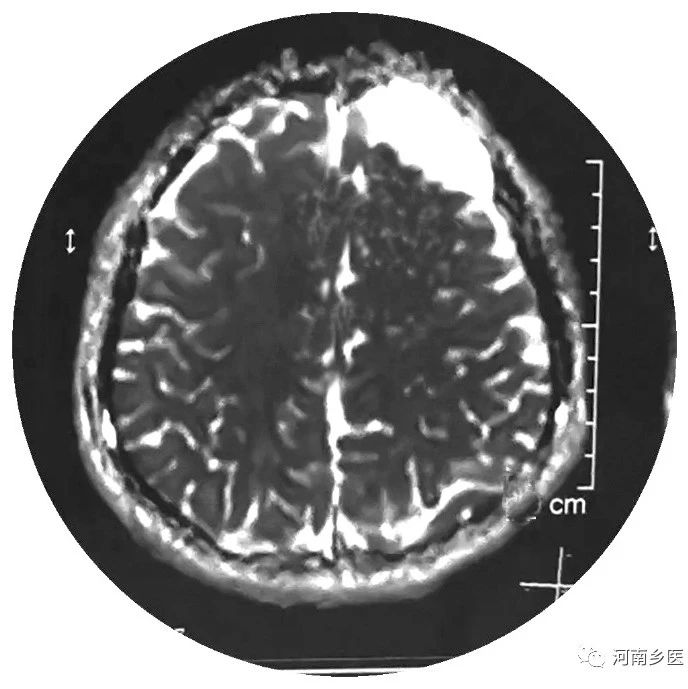

小儿蛛网膜囊肿的治疗

蛛网膜囊肿是颅内一种良性的、非遗传性的囊性占位病变,常见于颅中窝、桥小脑脚、鞍上区和颅后窝。蛛网膜囊肿与感染